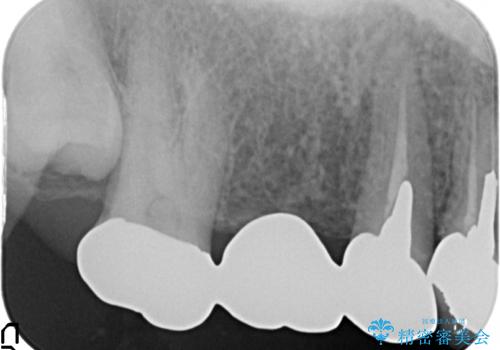

- 右上のブリッジでものを咬むと違和感があり、歯茎に膿の出口もできているので診て欲しいといらっしゃった方の症例です。

右上の567ブリッジを外したところ、右上5は歯根破折により保存不可能だったため、右上56部にインプラントを埋入し欠損補綴を行いました。

また右上5部に関しては抜歯時に歯槽堤保存術(抜歯窩に人工骨の填入を行う手術)を行い、骨の欠損を最小限に止めています。